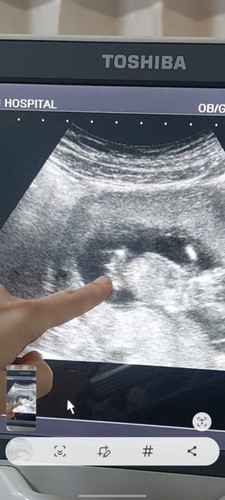

เพศลูก จากการซาวด์ 13 week

สวัสดีค่ะแม่ๆ แม่ได้ไปฝากครรภ์เป็นที่เรียบร้อยและซาวด์ ตอนแรกหมอบอกเป็นน้องผู้หญิง พอตอนท้ายเริ่มไม่แน่ใจแล้ว ว่าผู้หญิงหรือป่าว 🤣 แม่ๆว่าผู้หญิงหรือผู้ชายคะ ขอบคุณสำหรับคำตอบแม่ๆนะคะ ไม่ว่าน้องจะเป็นชายหรือหญิง แม่ก็ดีใจมากๆเลยค่ะ❤️👶